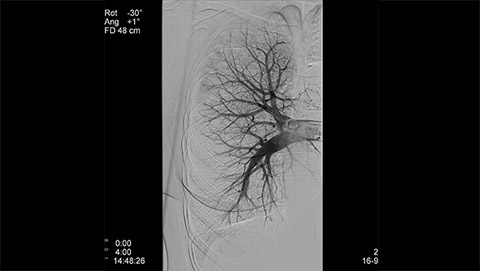

Dynamic 3D Roadmap provides a sustainable 3D roadmap to support interventional procedures. Dynamic 3D Roadmap matches the real-time 2D fluoroscopy images with the 3D-RA reconstruction of the vessel tree. It provides a 3D real-time insight of the advancement of the guide wire, catheter and coils through complex vessel structures. The Unsubtracted 3D Roadmap option reduces subtraction artifacts caused by patient breathing and movements, providing a clear roadmap during abdominal and thoracic interventions.

Live 3D Roadmap allows you to follow the advancement of guidewires, catheters and coils in real-time. It automatically adapts in real-time to changes in C-arm angulation and rotation, table movement, field of view and source-image distance.

XperCT extends the capabilities of the interventional suite offering CT like imaging to visualize bone, soft tissue and vessels in case of contrast enhanced acquisition. XperCT supports fast abdominal protocols with 5 to 8 seconds acquisition time for excellent image quality while significantly minimizing respiratory artifacts. The XperCT 3D volume is displayed automatically within 8 to 15 seconds after the acquisition and confirms selective targeting of hepatic lesion and helps avoid untargeted embolization and drug delivery.